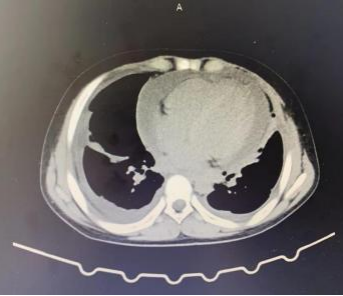

近日,贵阳市妇幼保健院儿童重症医学科(PICU)收治一位外院转诊的患者。该患者年仅13岁,咳嗽、腹痛5天。该院PICU医师立即进行了相关查体及检查,发现该患者双肺呼吸音粗,双下肢呈非凹陷性水肿。同时辅助检查提示双肺散在絮状密影,双肺胸腔少量积液,伴心脏明显增大,心包大量积液。大量的心包积液导致患者开始出现呼吸困难,剑突下疼痛等症状,救治刻不容缓。

根据患者病史及中心实验室检测报告在PICU、心脏外科、药剂科联合会诊后,确诊该患者为并殖吸虫感染者,及时优化治疗方案,予以吡喹酮口服治疗。在吡喹酮仅治疗2天,患者心包积液较前明显减少,逐渐监测心包闭式引流管未见液体引出,复查CT提示患者明显好转,已达临床出院标准。